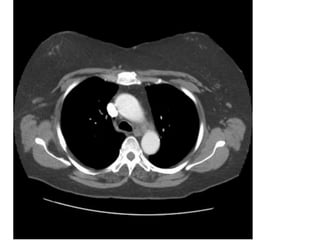

HÌNH 4

1, Trachea. 2, Rib. 3, Brachiocephalic artery. 4, Left brachiocephalic vein .

5, Pectoralis major muscle. 6, Pectoralis minor muscle.

7, Left common carotid artery. 8, Left subclavian artery,

4 10, Scapula. 15